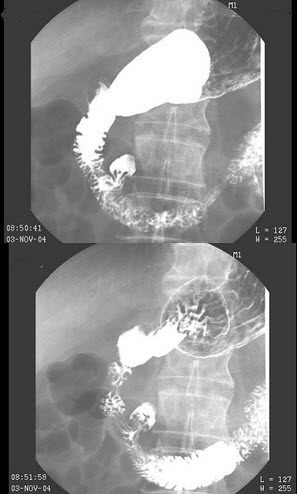

9、单项选择题

男,32岁,中上腹空腹痛,进食后缓解,剑突下轻度压痛,钡餐检查如图,最可能的诊断是()

A.十二指肠癌

B.十二指肠憩室

C.十二指肠球部溃疡

D.十二指肠节段性肠炎

E.十二指肠结核